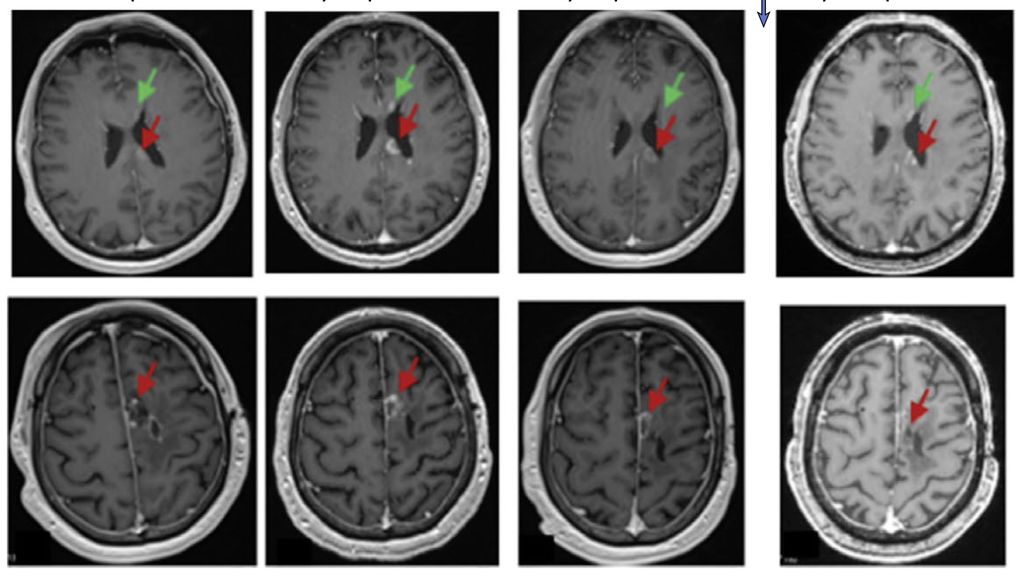

«Zu den Herausforderungen bei diesen Tumoren gehören die Heterogenität der exprimierten Tumorantigene und das immunsuppressive Tumormilieu», erklärte Prof. Dr. med. Denis Migliorini (Genf, Schweiz). Im vergangenen Jahr erregten verschiedene Publikationen zum Einsatz von CAR-T-Zellen beim Glioblastom grosse Aufmerksamkeit. Darunter war eine PhaseI-Studie zu intrathekal verabreichten CAR-T-Zellen, die sowohl gegen den epidermalen Wachstumsfaktor-Rezeptor (EGFR) als auch den Interleukin-13-Rezeptor-α2 (IL13Rα2) gerichtet sind (Abb.1).3

Abb. 1: Beispiel der MRT eines Patienten mit Glioblastom von einem Monat vor Verabreichung der CAR-T-EGFR-IL13Rα2-Zellen (Dosis-Level 2) bis zu drei Monaten nach der Verabreichung der CAR-T-Zellen. Axiale Gadolinium-verstärkte T1-gewichtete Bilder zeigten am Tag –1 vermehrt verstärkte Krankheitsherde, auch im Corpus callosum (oberes Feld, roter Pfeil), entlang der ependymalen Oberfläche des linken Seitenventrikels (oberes Feld, grüner Pfeil) und um die der linken frontalen Resektionshöhle (unteres Feld, roter Pfeil). Am Tag +1 aufgenommene Bilder, die vor der Verabreichung von Steroiden aufgenommen wurden, zeigen einen Rückgang an allen Stellen. Die Läsionen waren am Tag +28 stabil und blieben zum 3-Monats-MRT-Zeitpunkt unverändert (Quelle: Bagley SJ et al. 2024)3

«Wie wir anhand der Daten der ersten sechs Teilnehmenden dieser Studie gesehen haben, zeigte die Behandlung eine unmittelbare, potente Antitumoraktivität», so der Redner. Allerdings war die Ansprechdauer kurz und es wurde eine signifikante, wenn auch in allen Fällen reversible Neurotoxizität beobachtet. Prof. Migliorini und sein Team suchten gezielt nach weiteren Antigenen, die als Zielstrukturen für eine CAR-T-Zell-Therapie infrage kommen. Ihre Wahl fiel auf PTPRZ1 («protein tyrosine phosphatase receptor type Z1»).4 Zudem entschieden sie sich für eine mRNA-basierte Herstellung der CAR-T-Zellen, im Gegensatz zum üblichen Vorgehen der viralen Transduktion.